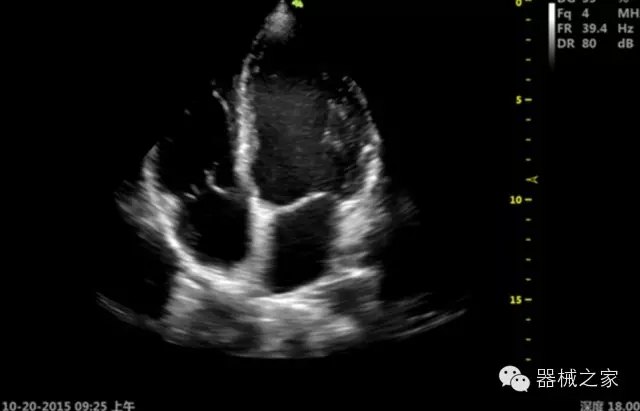

·ICU/CCU;

·飛依諾特有心臟純凈波探頭提供更好的穿透力和彩色敏感度,以及結(jié)合TView梯形拓展改善困難病人深部組織成像;

·獨有RF敏感血流使得心臟血流完美呈現(xiàn);